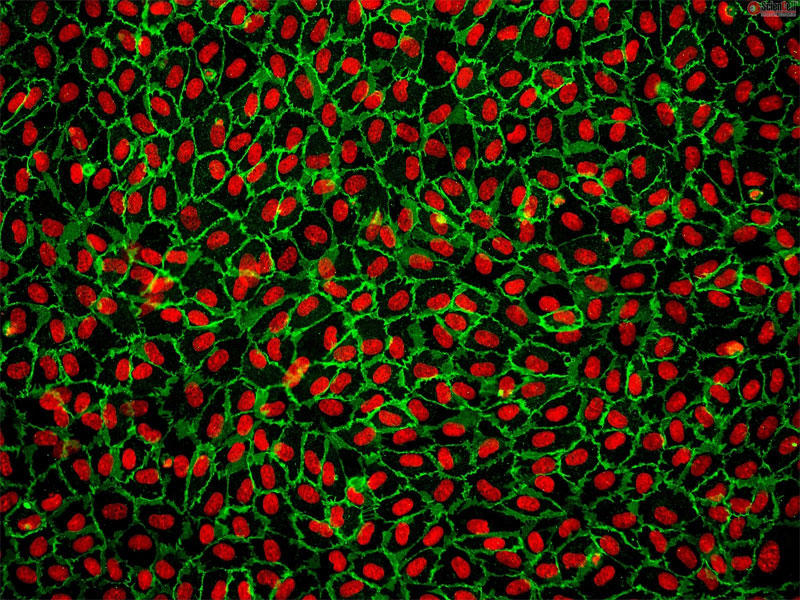

ScienCell社では、HUVEC(ヒト臍帯静脈内皮細胞)を販売しております。

HUVECは、循環器領域における医薬品開発、高分子輸送、血管形成および血管新生の研究などの実験に使用されています。